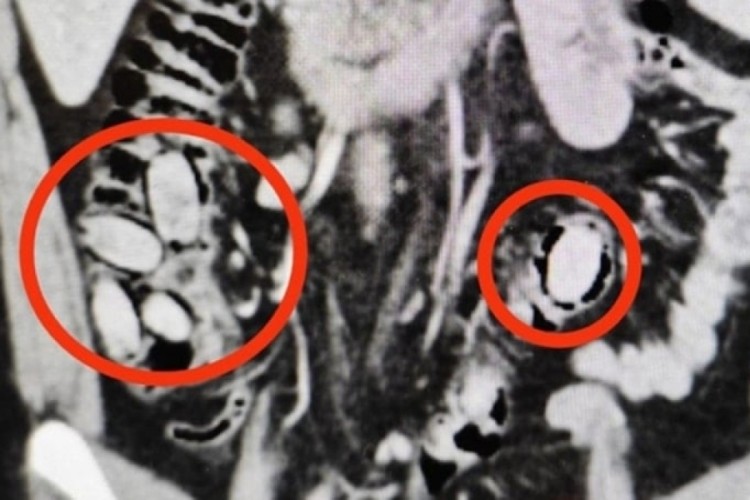

Eskişehir'de midesinde 44 kapsül sentetik uyuşturucu olduğu belirlenen yabancı uyruklu şüpheli tutuklandı.

Hastane kontrolüne götürülen 25 yaşındaki S.A.'nın midesinde 44 kapsül sentetik uyuşturucu olduğu belirlendi.

Operasyonla midesindeki kapsüller çıkarılan S.A., hastanedeki tedavisinin ardından sevk edildiği adliyede çıkarıldığı hakimlikçe tutuklandı.